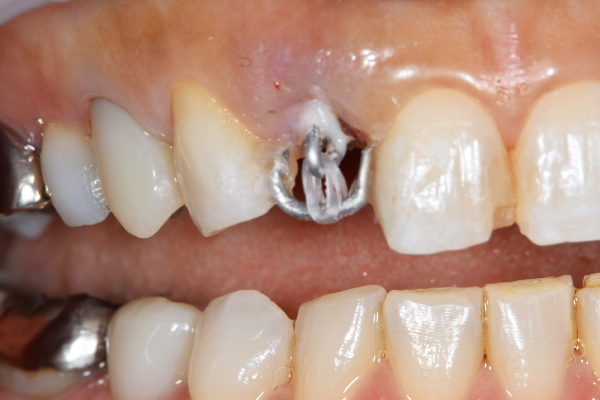

治療前で残存歯質がほとんどみられません。

残存歯質はないが、歯根は長いことを確認。

MTM中。頬側には審美面の回復のために仮歯がついています。

歯からはフック、隣り合った歯にはワイヤーが渡してあります。そこにゴムをひっかけて歯を挺出します。